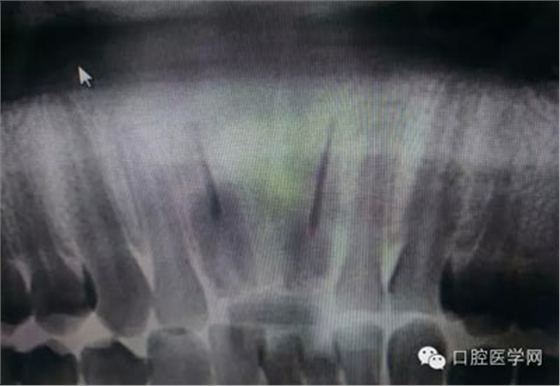

根管再治療是我們比較頭疼的,尤其是那些冠修復(fù)過的,我們有很多的麻煩需要去溝通,比如可能導(dǎo)致的側(cè)穿、可能沒有看到的腐質(zhì)、可能導(dǎo)致的崩瓷,或者是后期可能出現(xiàn)冠折......這些需要我們和患者好好的溝通。全瓷冠還好些,金屬冠根測(cè)的時(shí)候很是麻煩,總之我們做修復(fù)的時(shí)候不要單純的追求速度,追求效益,適當(dāng)?shù)淖⒁庀挛覀兊幕A(chǔ)治療和設(shè)計(jì)。